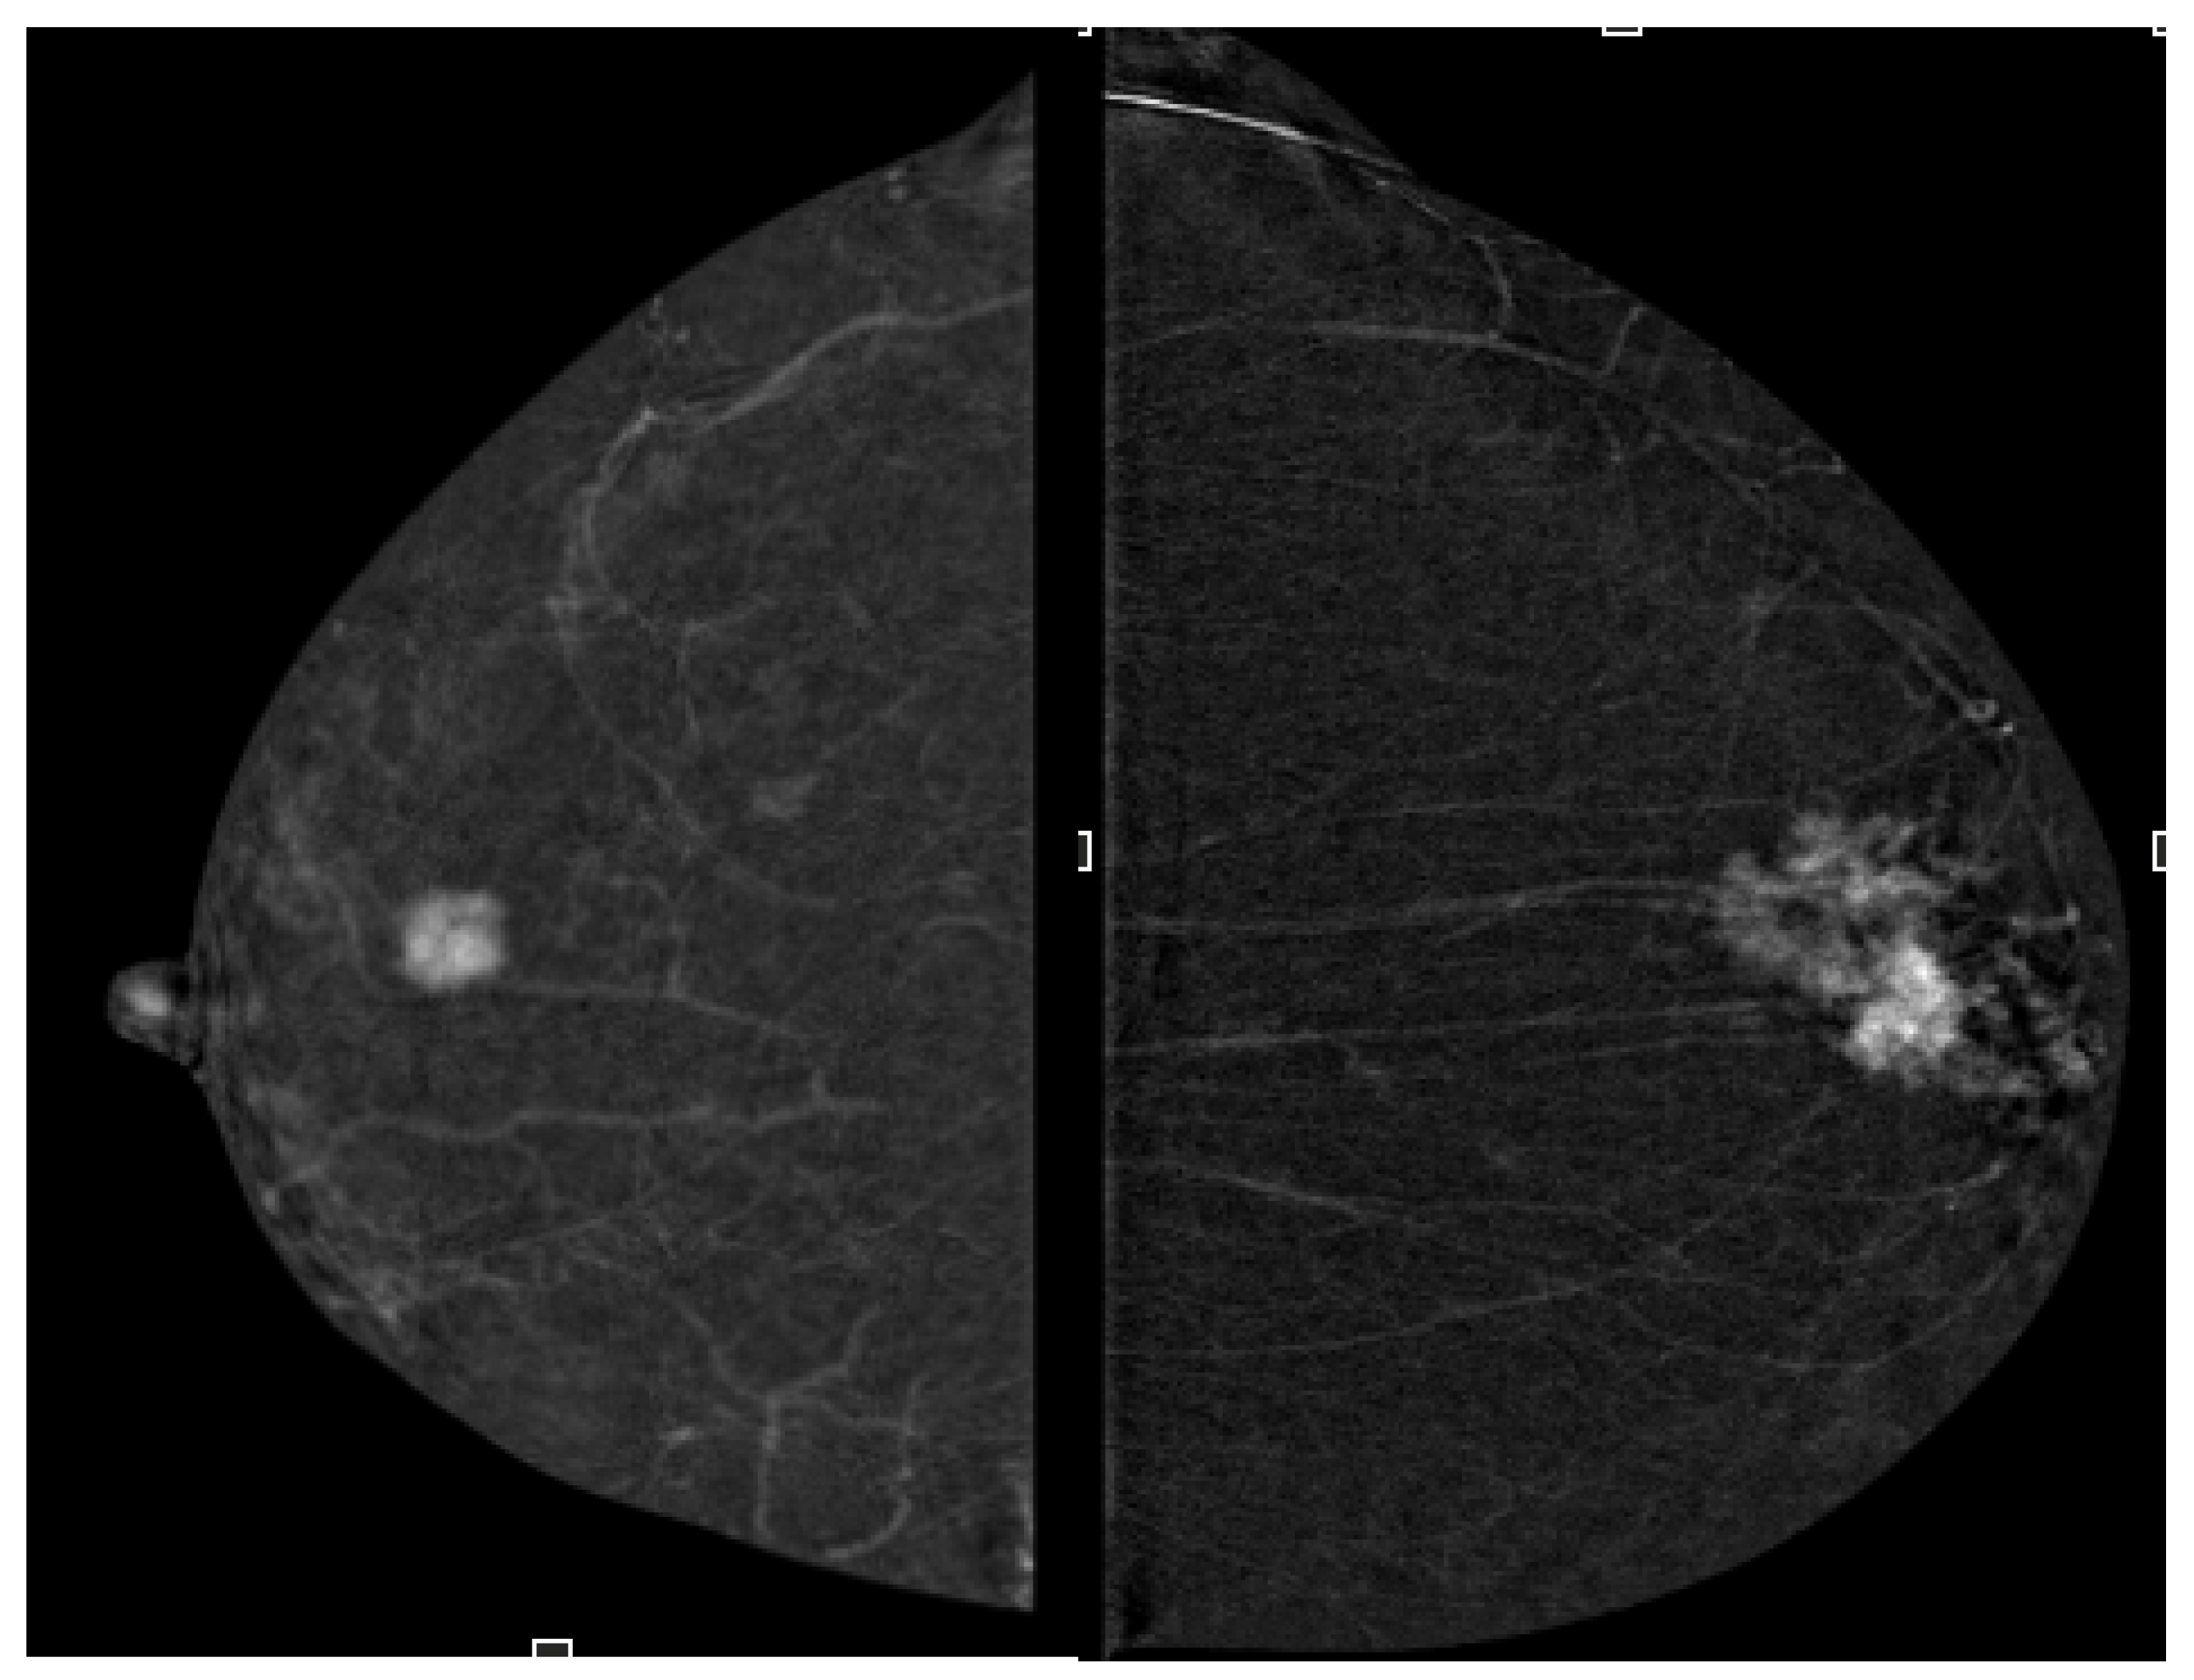

3.3. Correlation of Ki-67 and Enhancement Intensity

3.4. Correlation of Contrast Homogeneity and Tumor Grade